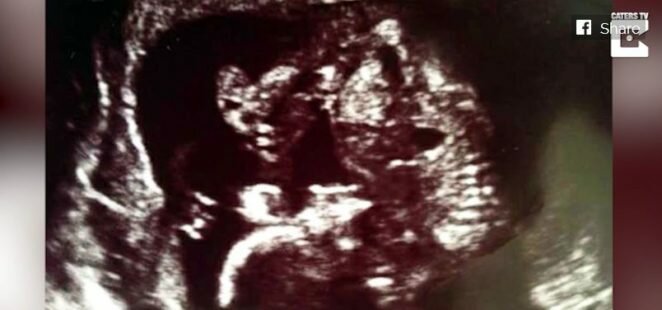

Nagle jednak pojawił się lęk. Brzuch Shaniece rósł bardzo szybko. Był stanowczo za duży jak na ten okres ciąży. Cała trójka rodziców poszła na badanie USG, a wtedy, ku zaskoczeniu wszystkich okazało się, że dziewczyna spodziewa się nie jednego, a dwójki dzieci. Młode małżeństwo było zaskoczone i szczęśliwe, zajęło się zakupami dla dwójki dzieci. Nie był to jednak koniec niespodzianek jakie ich czekały.

Kolejne badanie USG okazało się jeszcze bardziej szokujące – okazało się, że Shaniece spodziewa się trojaczków. Małżeństwo było zszokowane, ale szczęśliwe. To był cud! Tak bardzo bali się, że nigdy nie zostaną rodzicami, a okazało się, że na świat przyjdzie aż trójka ich dzieci.